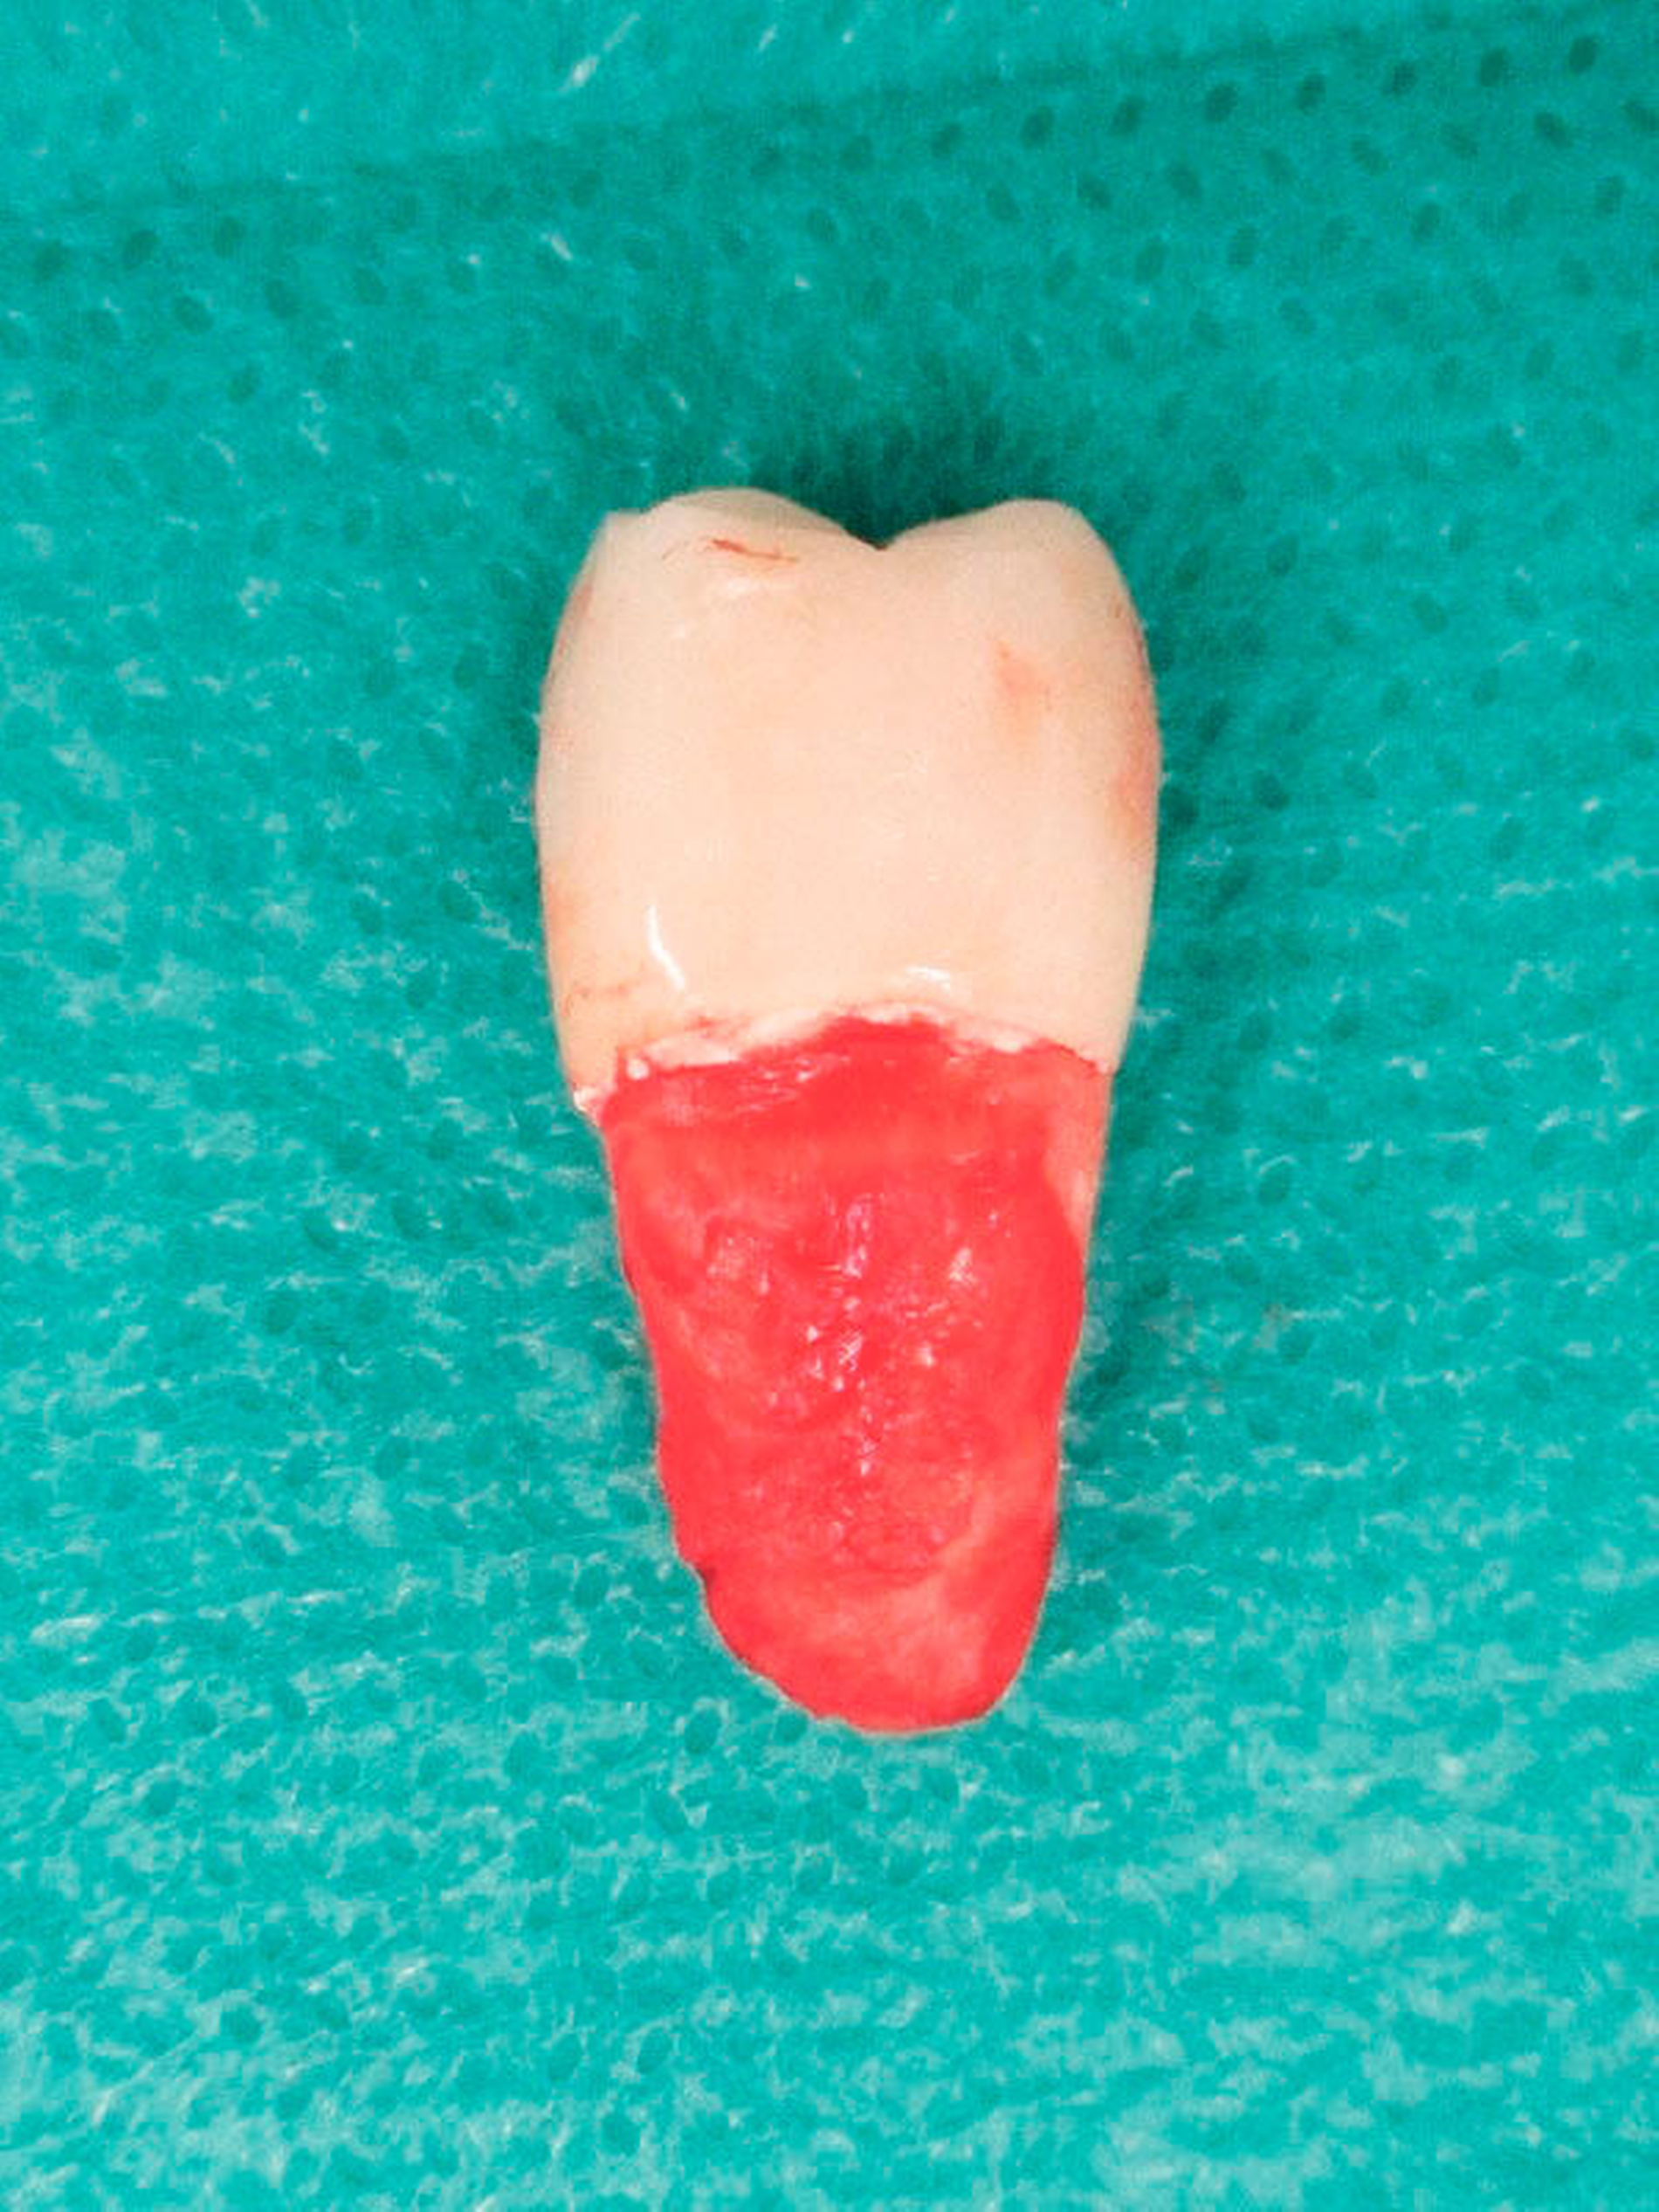

Nach Freilegung und prothetischer Versorgung im August 2015 waren die Titanimplantate und der dazwischen befindliche Zahn 15 zwei Jahre lang beschwerdefrei in situ – bis Ende April 2017 der Zahn 15 beim Kauen eines Fleischstücks spontan in die Kieferhöhle luxierte (Abbildungen 1 und 2).

Eine Sinusitis maxillaris bestand nicht und die Patientin litt unter keinerlei Schmerzen. Allein die unterbrochene Zahnreihe störte.